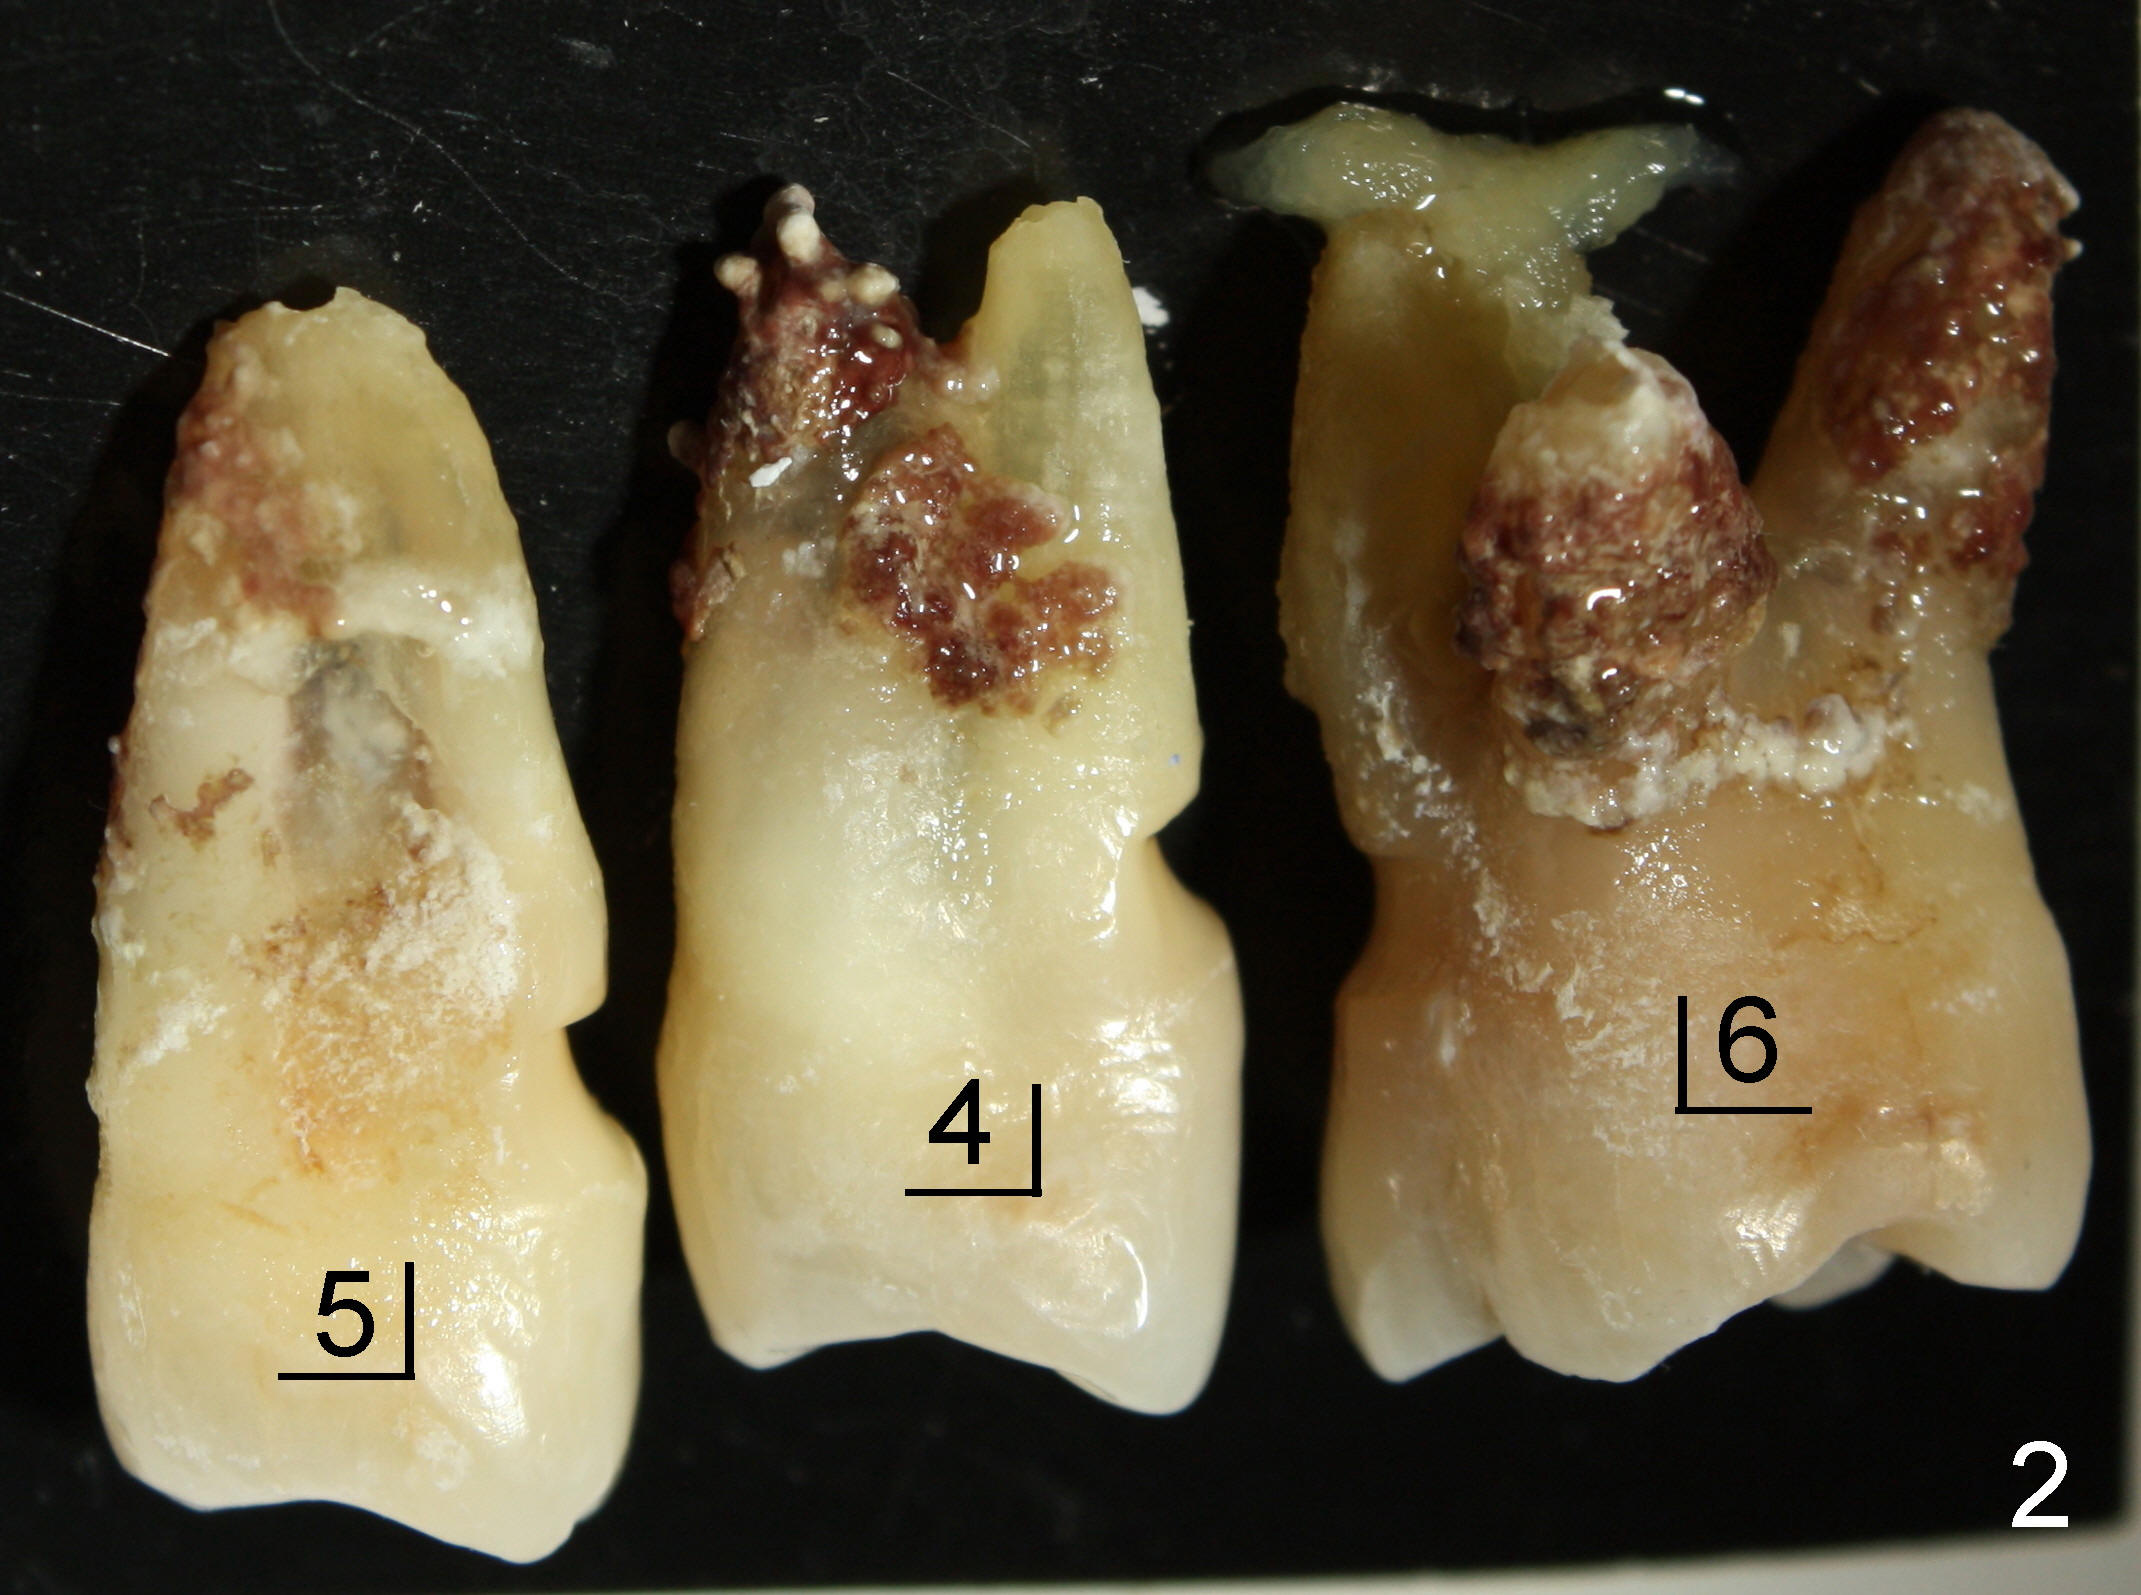

五十来岁吴先生牙周病严重(图一),尤其右上4,5,左上6,最后拔除(图二:远中面观),可见口腔卫生差。先做局部托牙,三年后又失去几个下牙,终于同意植牙。主要困难是上颌窦很低,最好先做上颌窦植骨,但是他胆子特小,多做一个手术对他来说是很大精神创伤,所以壮着胆子先做左上6植牙(图五:7x11mm,torque > 60 Ncm),虽然远中底板不可观(图五箭头之间),但是植牙很牢靠。右侧上颌窦底板更薄,估计不做上颌窦植骨不行,给他吹风说需要做一个手术才能植牙,他竟然同意。但是突然他的托牙(framework removable partial denture)断裂了,断在金属部分(major connector: anterior and posterior bars),说明他咀嚼力如此大,技工室说激光焊接没有保证。我们不得不取消上颌窦植骨,因为它会延迟植牙五六个月,所以我们再次铤而走险在右上第一双尖牙(图三:4, 4x20mm,> 60 Ncm)和第一磨牙(6, 6x11mm,> 60 Ncm)植牙,一个月后在两者之间再植入一个(图四:5,4.5x14mm,> 60 Ncm)。尽管第一磨牙植牙远中骨板相当薄(图四箭头之间),但是它很紧,可能与上颌窦底板坚硬有关。在病人多次要求下,半个月后就装上基牙(图六:2,4,5,6),放置临时牙冠,后三者连在一起(好像牙桥,增加稳定性),这样病人可以正常吃饭。一周后,侧切牙临时牙冠脱落,病人回诊所重新粘固,而右上牙桥仍稳定。